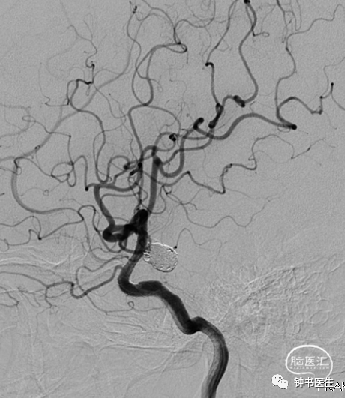

术后6个月DSA复查:动脉瘤无残留、复发,治愈!

术后13个月DSA复查:动脉瘤无残留、复发,治愈!